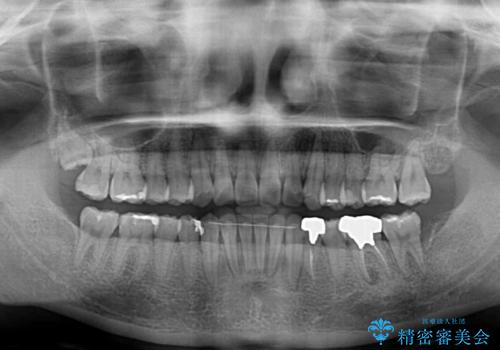

- 前歯のデコボコと深い咬み込みを気にして来院された患者様です。

インビザラインを用いて、前歯の叢生を解消するとともに、深い咬み合わせ(ディープバイト)を改善していくこととしました。

奥歯を後方に直立させることで深い咬み合わせを改善を図り、隠れていた下顎前歯が見えるほどになりました。